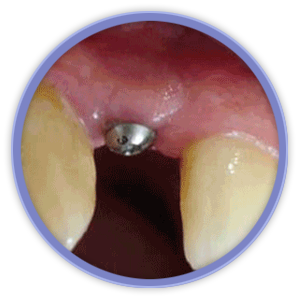

El aspecto más revolucionario en este ámbito fue la aparición de los implantes dentales que son unos pequeños bloques de titanio, con forma de raíz dental, que se insertan dentro del hueso mandibular o maxilar del paciente y sirven de sujeción para dentaduras, puentes o coronas, mejorando así la calidad de vida y aumentando las posibilidades de tratamiento de los pacientes.

Mediante técnicas de rehabilitación en un solo día, hacemos posible que el paciente salga de la consulta con los implantes y sus dientes, provisionales fijos, colocados.

La magnificación de la imagen mediante lupas o microscopio dental nos permiten niveles de acabado y de precisión mucho más exigentes. Actualmente la importancia de la estética gingival (encías), ha obligado a desarrollar técnicas de regeneración de hueso y tejidos blandos, que complementan a las cirugías de implantes entre otras.